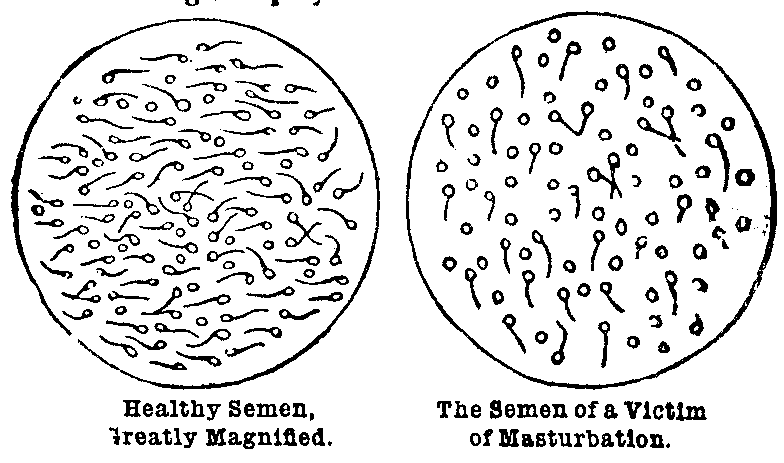

1. Habit.—Our real strength in life depends upon habits formed in early life. The young man who sows his wild oats and indulges in the social cup, is fastening chains upon himself that never can be broken. The innocent youth by solitary practice of self-abuse will fasten upon himself a habit which will wreck his physical constitution and bring suffering and misery and ruin. Young man and young woman, beware of bad habits formed in early life.